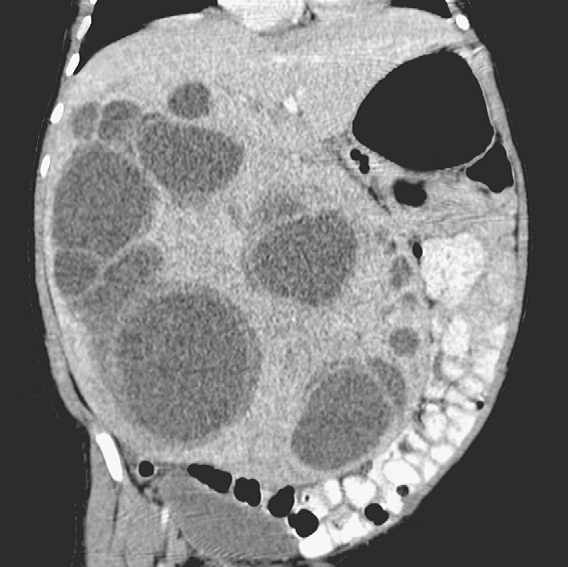

Mesenchymal Hamartoma of the Liver

Large, multilocular, cystic masses with thin internal septations